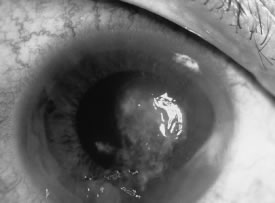

In the early stages of infection, filamentous fungi produce signs that are readily distinguishable from yeast or bacterial keratitis. The most distinctive sign is the presence of delicate, fine, feathery, opalescent, gray-white or yellow-white material in the anterior stroma, surrounded by scant cellular infiltrate or edema (Fig. 1). The epithelium may be intact. The overlying epithelium may be granular and the surface elevated and irregular in contour. Linear infiltrates typically extend into the adjacent stroma. Multiple discrete opacities may develop outside the perimeter of the principal focus of inflammation, either separated by clear stroma or linked by fine linear collections of inflammatory cells and material (Figs. 2 and 3). In the absence of inflammation in the adjacent stroma, branching hyphal fragments may be visualized by biomicroscopy (Figs. 4 and 5). Confocal microscopy may also detect hyphal elements within the stroma.28,29 Peripheral infection resembles noninfectious marginal infiltrative and ulcerative keratitis (Fig. 6). Multifocal keratitis may develop after contact lens wear or injury by multiple projectiles (Fig. 7). In the early stages, iritis is present and the intraocular pressure remains normal. Inappropriate, empirical therapy of fungal keratitis with topical fluoroquinolone or aminoglycoside antibiotics may suppress or eliminate the superficial elements but allow extension of the organisms into the stroma because these agents may possess selective antifungal activity.4,30,31

There is no distinguishing clinical sign by which to recognize the genus or species of the infectious filamentous fungus. F. solani is the most virulent organism and typically produces rapidly progressive infection characterized by epithelial and stromal ulceration, dense stromal necrosis, abundant cellular infiltrate, and edema in the adjacent stroma and hypopyon (Figs. 8 and 9). Delicate feathery components are transient. Individual hyphal fragments are rarely visualized. Infection by certain species of Aspergillus and Scedosporium (Figs. 10 and 11) resembles F. solani keratitis and progresses rapidly. Infection by less virulent organisms, such as Curvularia and Alternaria species, produces small, focal (less than 3-mm diameter) areas of nonnecrotizing stromal inflammation with delicate feathery borders (see Fig. 1 and Fig. 12). Macroscopic pigmentation may develop in keratitis caused by Alternaria, Curvularia, and other dematiaceous fungi (Fig. 13).4,11,14 The central component may progress to dense, opaque, gray-white suppuration in the deep stroma without enlargement in total area and may be accompanied by mild inflammation in the adjacent stroma. Iritis is minimal to moderate. Infection caused by other, relatively less virulent organisms resembles herpes simplex or noninfectious keratitis (Fig. 14).